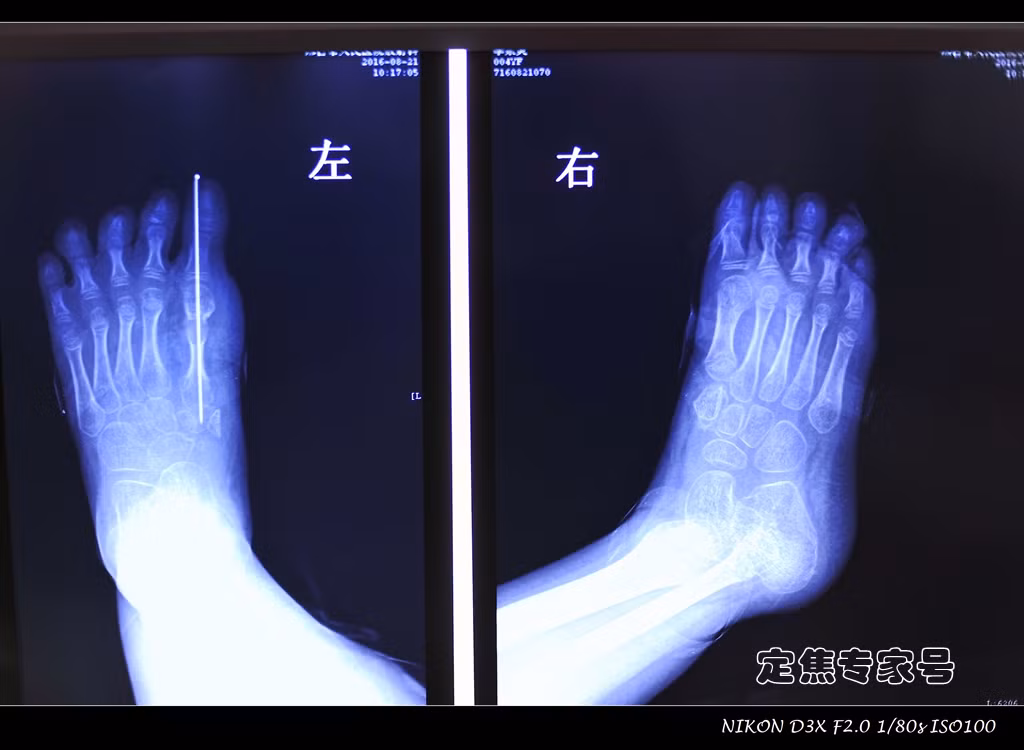

Hình ảnh ghi lại chân một bé gái Trung Quốc 4 tuổi bị dị tật bẩm sinh có 13 ngón, chân trái của bé có 7 ngón, chân phải 6 ngón. Kể từ khi được sinh ra, cha mẹ bé đã sống trong sự đau khổ vì lo lắng dị tật sẽ tiếp tục biến chứng, cùng với đó là sự nhạo báng của miệng lưỡi người đời.

Không chỉ sở hữu số ngón chân nhiều bất thường, bàn chân của bé gái còn mở to biến dạng, ảnh hưởng đến đi lại. Mẹ bé cho biết, ngay cả những đôi giày bình thường bé cũng không thể đi vừa. Sau khi kiểm tra kỹ lưỡng, các bác sỹ kết luận, dị tật bàn chân trong trường hợp lần này khá hiếm gặp, vậy nên Phó giám đốc bệnh viện Bắc Kinh đã trực tiếp tham gia vào cuộc phẫu thuật chỉnh hình.